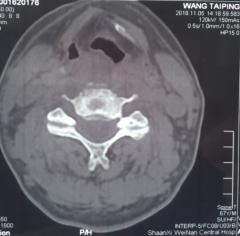

来市中心医院后,患者四肢肌力上肢1-2级,下肢1级。双下肢腱反射未引出。自胸骨柄以远躯干部位感觉减退。入院后给以各项常规检查,血常规显示白细胞计数12.54×109/L,中性粒细胞绝对值10.85×109/L,,中性粒细胞百分比86.5%,血沉22mm/h,超敏C反应蛋白69.4mg/L。空腹血糖13.88mmol/L。颈椎核磁检查显示颈4/5椎间隙狭小,颈4.5.6椎体T1像低密度,椎体前缘出现炎性浓集。入院初步诊断:颈椎体感染,合并椎间隙脓肿形成,四肢不软瘫,糖尿病II型。在治疗早期即给以广谱抗生素头孢哌酮舒巴坦钠静滴.3.0g,q8h;并口服莫西沙星片,0.4g,qd,使用阿卡波糖控制血糖。再次完善相关检查。全身放射性同位素骨扫描未见肿瘤表象。结核TB淋巴细胞斑点试验阴性,布氏杆菌滴度测定阴性。经治疗,患者体温平稳,血沉,超敏C反应蛋白水平下降明显。后期再次复查颈椎核磁,发现颈椎椎体4.5前缘形成更大的积液表现,椎管内也有形成。随后在B超定位下行颈前肿物穿刺抽吸术,抽出含血浑浊液2ml,分泌物抗酸染色阴性,常规染色图片发现多量的阳性球菌,细菌培养3未见细菌生长。